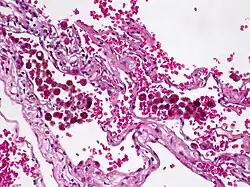

L'hémosidérose localisée est un dépôt d'hémosidérine (complexe protéique riche en fer) limitée à un tissu ou un organe. Elle s'oppose à l'hémosidérose systémique (ou hémosidérose généralisée). De façon générale, la surcharge en fer des tissus qui composent l'organisme, est appelée hémosidérose. C'est un phénomène extrêmement banal, en effet toute hématie ayant traversé la paroi d'un vaisseau par rupture de celui-ci (hémorragie) ou par érythrodiapédèse est détruite sur place par les macrophages qui vont élaborer du pigment ferrique à partir de l'hémoglobine[1]. Chaque hémorragie intratissulaire est donc vouée à laisser place à une plaque d'hémosidérose ; l'hémosidérose localisée se rencontre donc essentiellement dans les zones d'hémorragies anciennes[2].

L'hémosidérose localisée peut être systématisée à un organe et reste donc localisée comme par exemple l'hémosidérose pulmonaire, ou dans le cerveau où à la suite d'accident vasculaire cérébral elle constitue l'hémosidérose corticale[3].